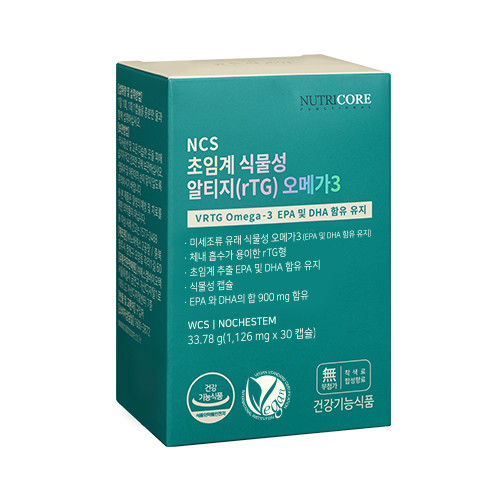

- 제조사: 뉴트리코어

- 특징: 고순도의 EPA와 DHA가 풍부해 혈중 중성지방 수치를 효과적으로 낮추며, 혈액순환을 촉진해 심혈관 질환을 예방하는 프리미엄 제품입니다. 특히 중년 이후 급격히 높아지는 심혈관 위험 관리에 최적입니다.

- 복용법: 하루 1회 식후 간편 섭취